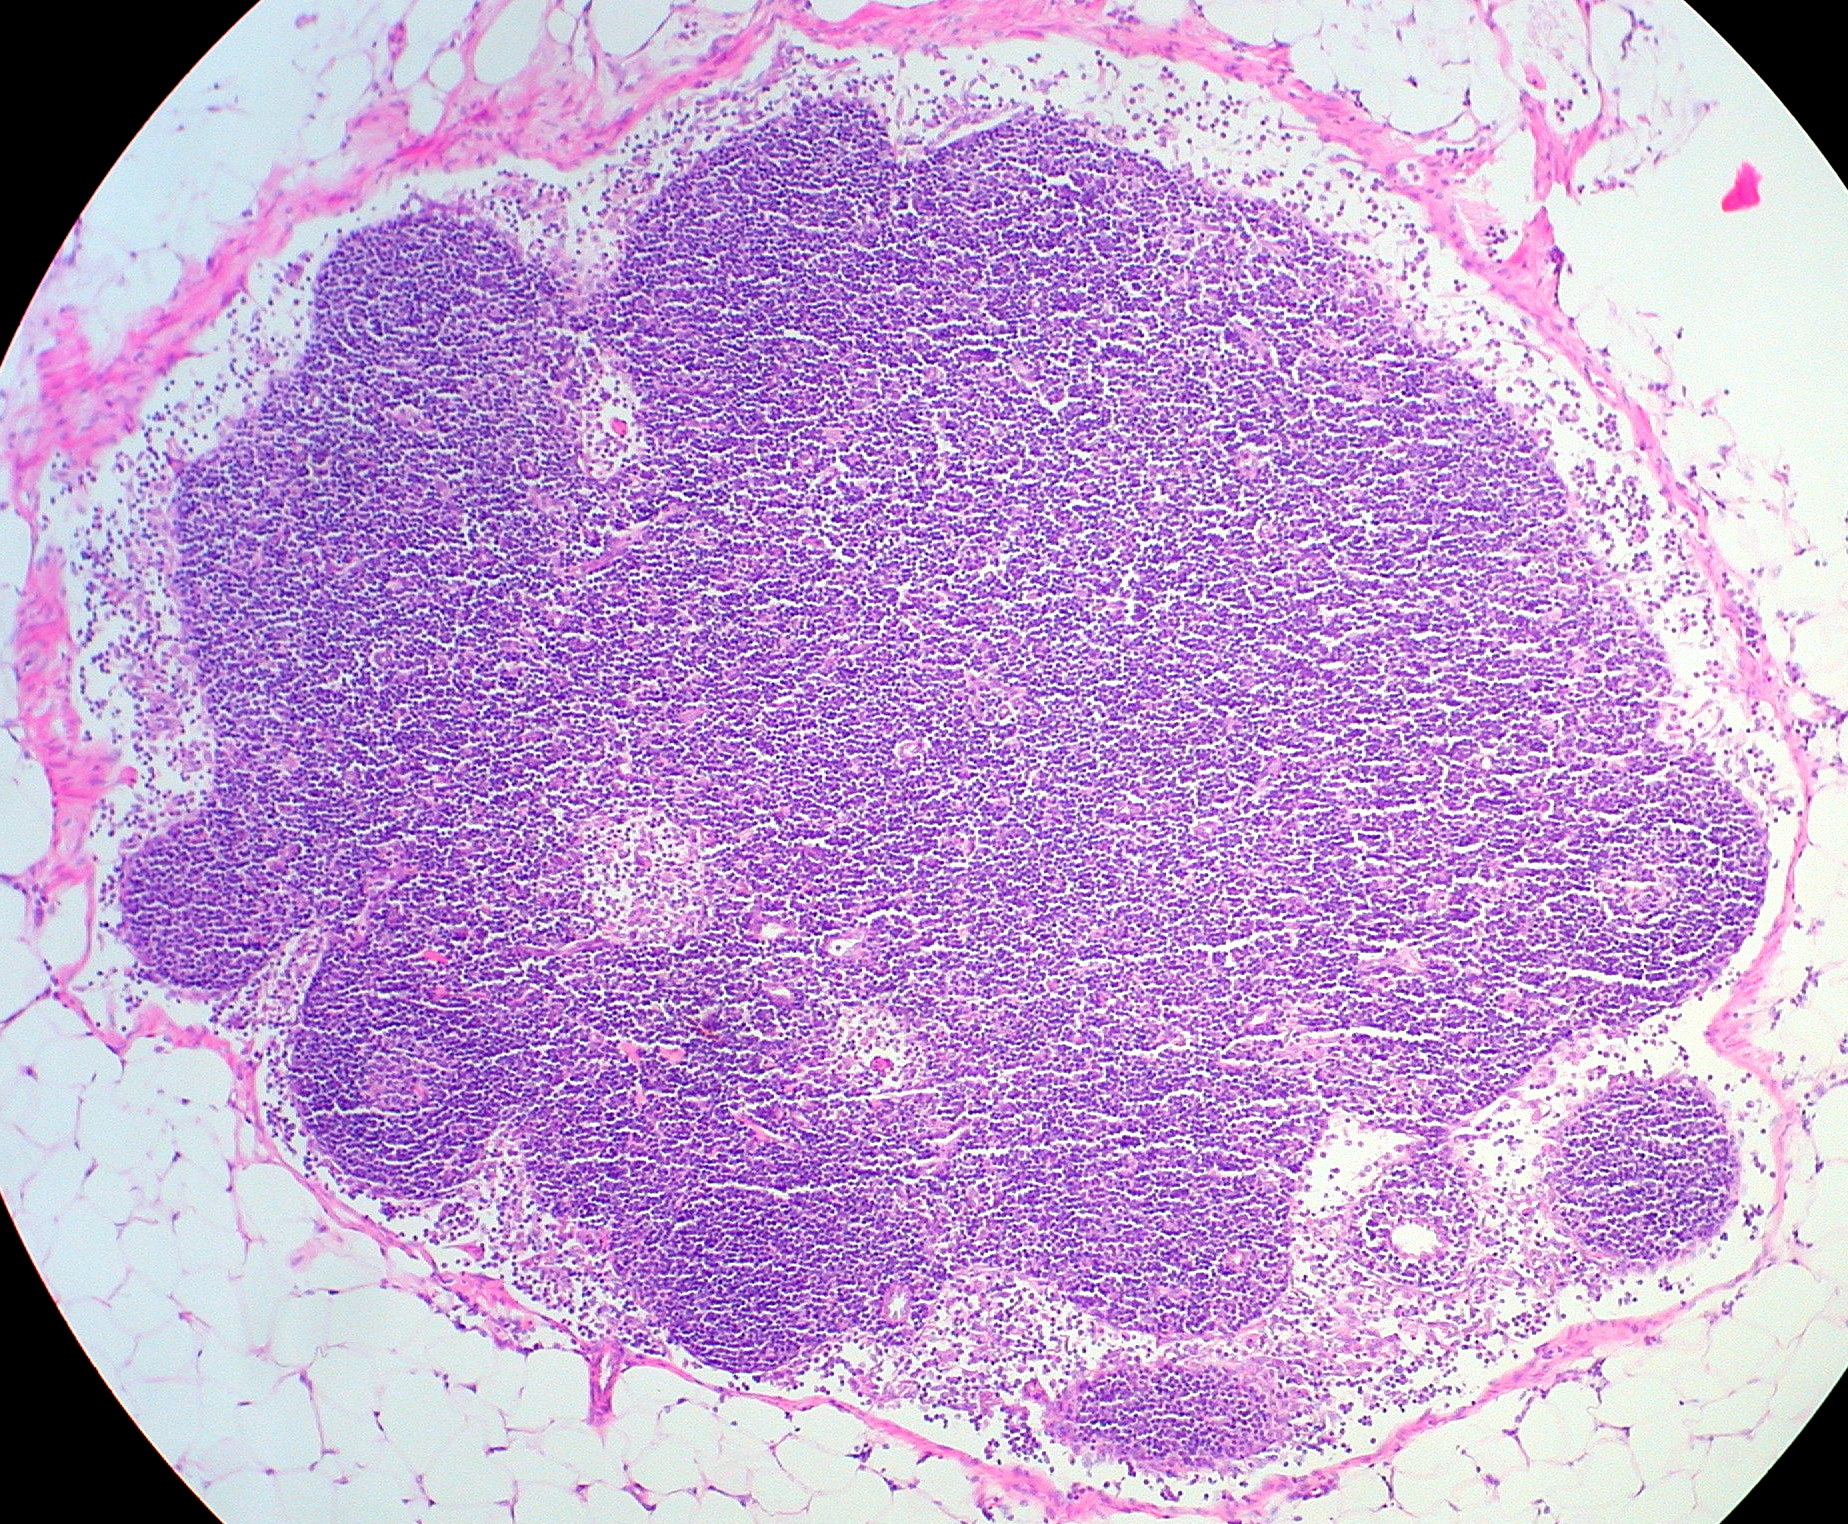

Histology of a lymph node

Histologie d’un ganglion lymphatique

Histología de un ganglio linfático

Histologie einer Lymphknoten

Гістологія лімфатичного вузла

Гистология лимфатического узла